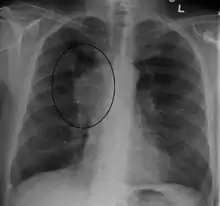

诊断 SVCS 的主要技术是胸X 光检查 (CXR)、 CT 扫描、支气管镜下经支气管针吸活检和纵隔镜检查。 [5] CXR 通常能够显示纵隔增宽,并可能显示 SVCS 的主要原因。 [5]